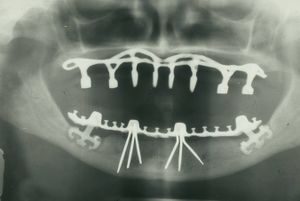

تكون الغرسة مفردة أو متعددة أو شاملة، ويميز في طب الأسنان بين أربعة أنواع من الغرسات: التثبيت بالغرسة عبر السن transdental fixation والغرسة تحت الغشاء المخاطي submucosal implant والغرسة تحت السمحاق subperiosteal implant والغرسة في العظم enossal implant.

أما النوع الثالث، فأول من جربه مولّر عام 1937، إذ قام بزرع شبك معدني تحت السمحاق على طول الحافة السنخية للفك السفلي، مع بروز أربعة مهاميز خارج الغشاء المخاطي إلى جوف الفم لتحمل الجسر التعويضي. طوَّر دال الطريقة عام 1943 فصنع الشبكة من الكروم - كوبالت، غير أن عدم التطابق الكامل بين سطح الشبكة وسطح العظم الحامل لها يؤدي إلى خلل التوزع في الضغط، مما دعا الباحثين إلى كشف العظم وأخذ طبعة حقيقية لسطحه، والعودة إليه بعد صنع شبكة مطابقة له، وهذا يعني اللجوء إلى عمليتين لتحقيق الغاية بما في ذلك من رض.